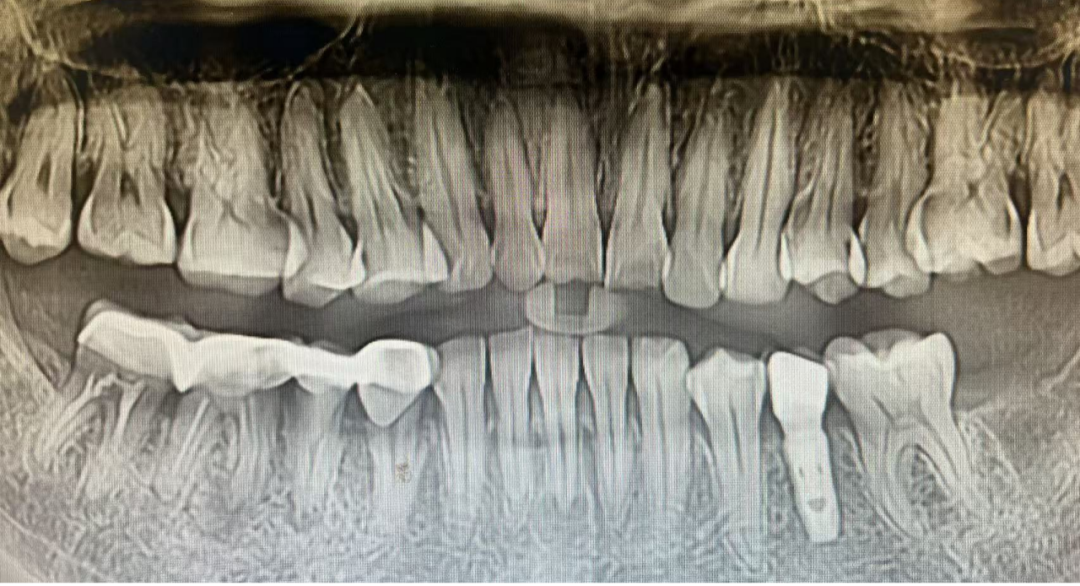

不同缺牙位点种植体X线影像

种植患者1年后口内复查照片及X线影像